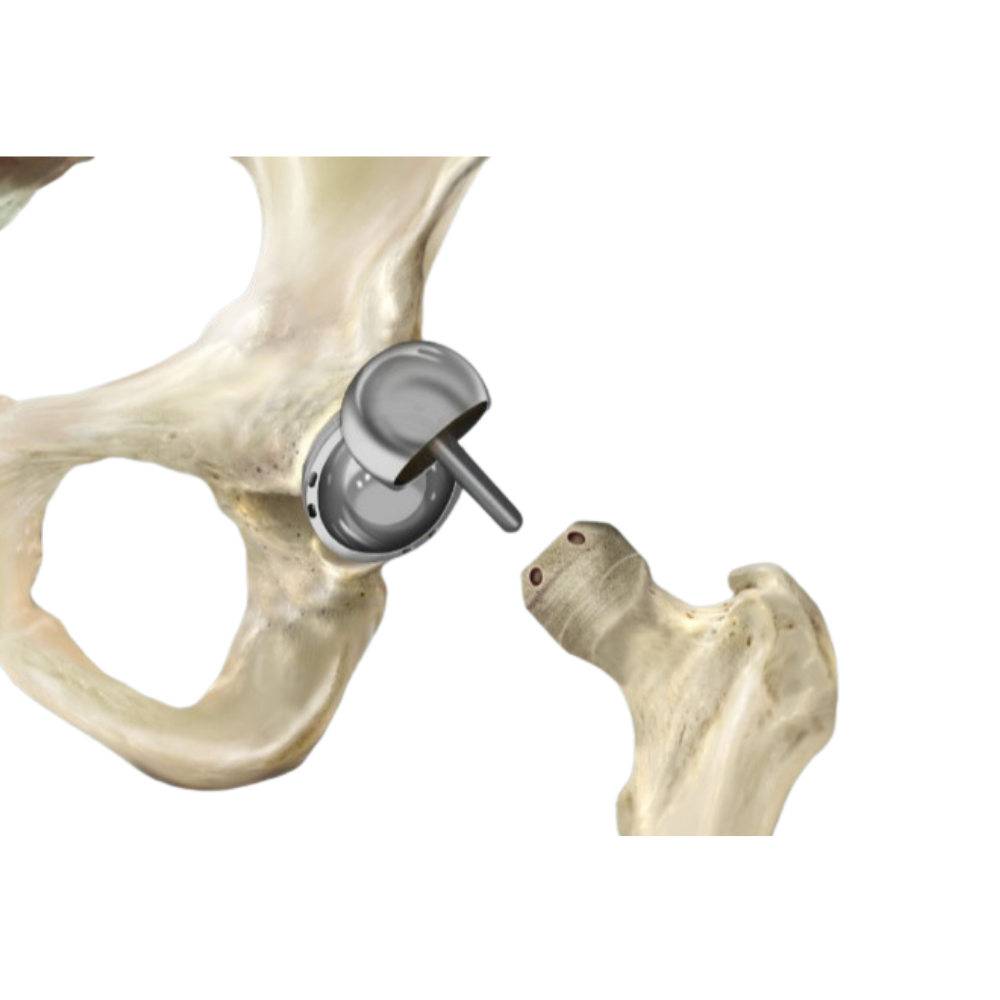

An alternative to full replacement where only the damaged joint surface is treated.

Preserves more bone and may be suitable for younger, active patients.